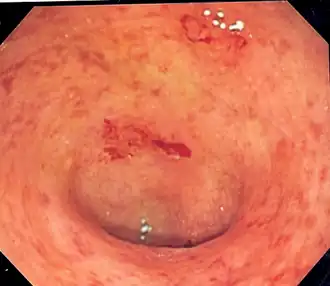

| Imagem endoscópica de um cólon sigmóide afetado por colite ulcerosa. Note o padrão vascular da granularidade do cólon e a friabilidade focal da mucosa. | |